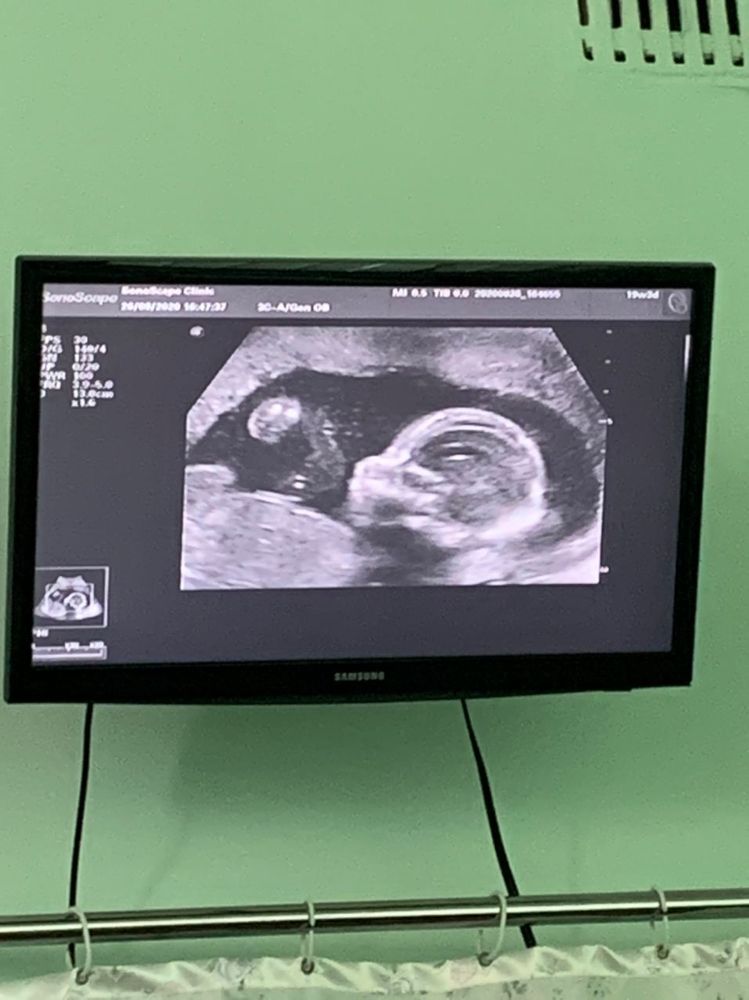

Наш второй скрининг доверила поснимать мужу. В итоге, ничего толкового и на память не осталось😄Зато теперь знаем, что у нас девочка❤️

Не помню, какого числа было УЗИ, на сегодня у нас 21-я неделя, развиваемся в срок. Кувыркается иногда очень бодренько, но подсчеты не веду. Пусть ребёнок развлекается, сколько ей хочется))